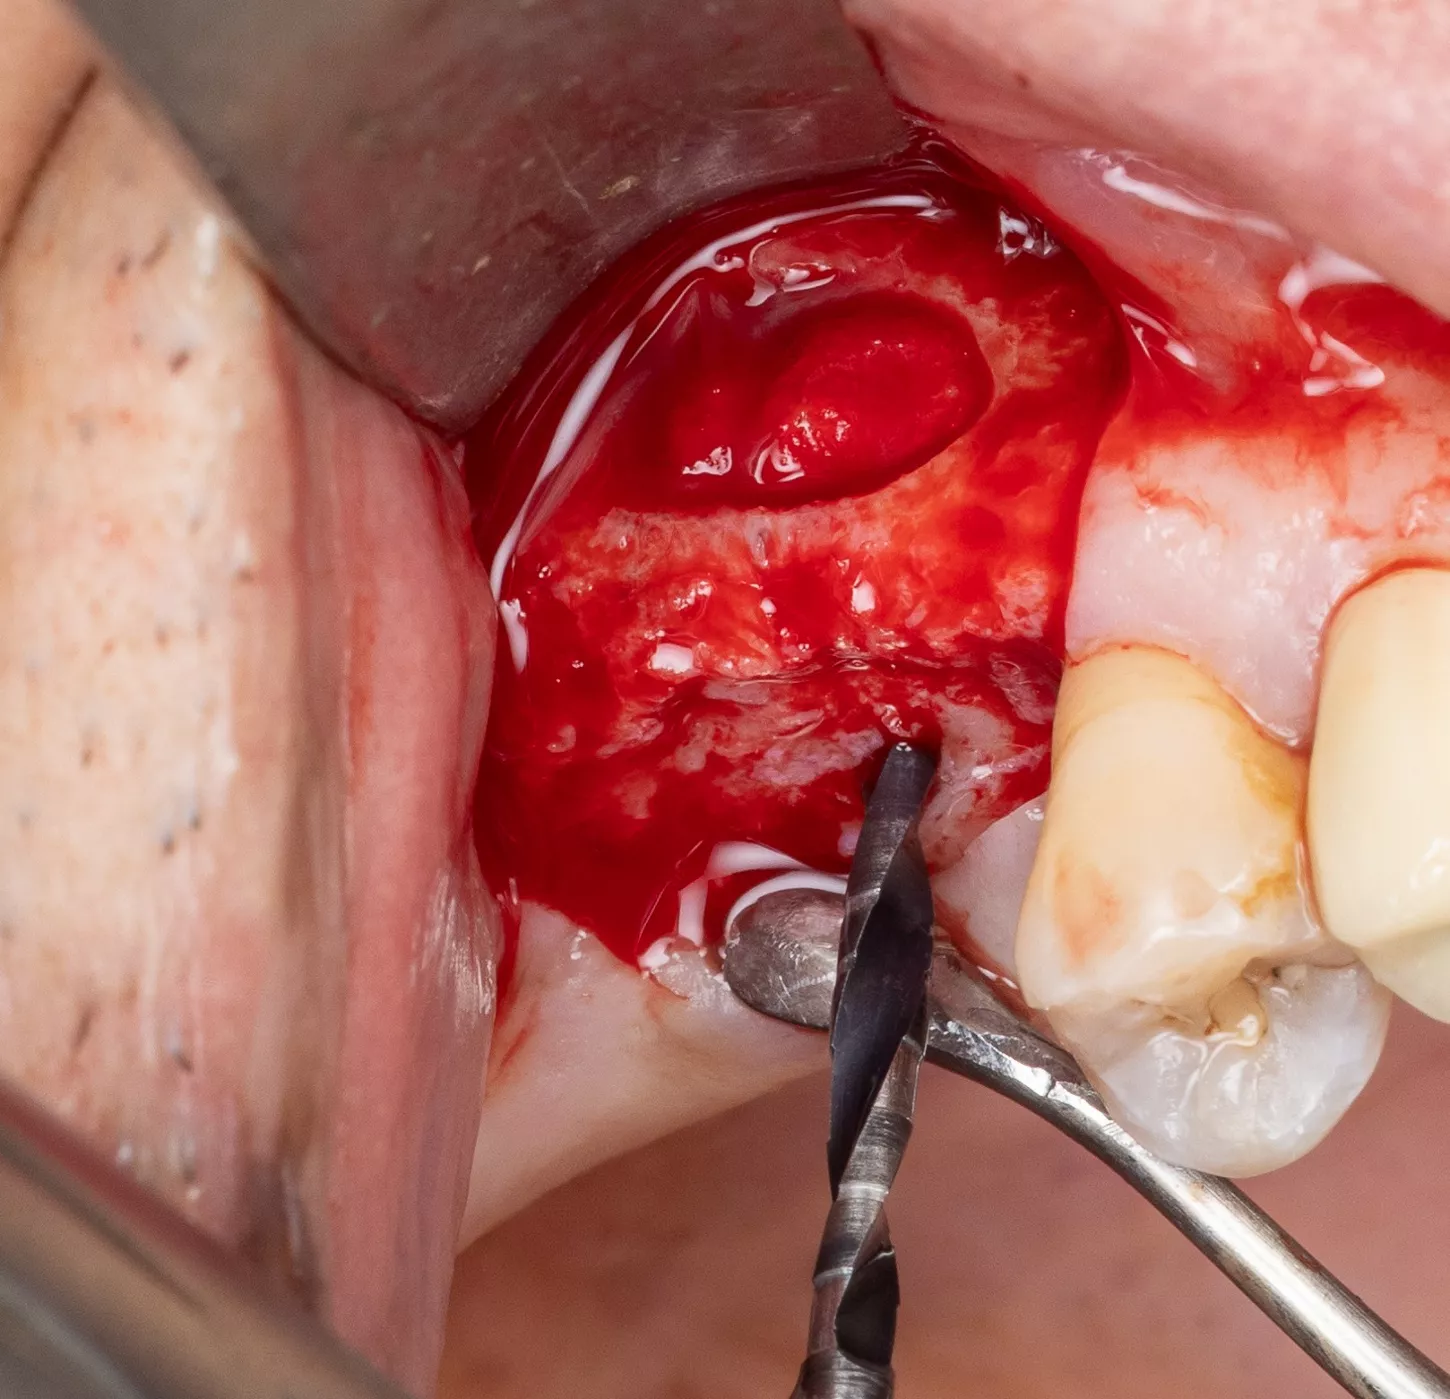

4. Sinus window : Subtractive osteotomy without preservation of the bone flap using a 2.5 mm diamond bur mounted on a surgical handpiece. The Schneiderian membrane (sinus mucosa) of slightly bluish grey color is exposed.

5. Initiation of lifting of the sinus mucosa through the inferior mesial window angle.

6. Placement of a saline-impregnated collagen sponge to assist the detachment by conferring increased but gentle and evenly distributed pressure.

7. Sinus mucosa detached.

8. Verification of the absence of mucosal adherence at the Beta angle and at the inter-sinus-nasal septum using a Freer sinus elevator.